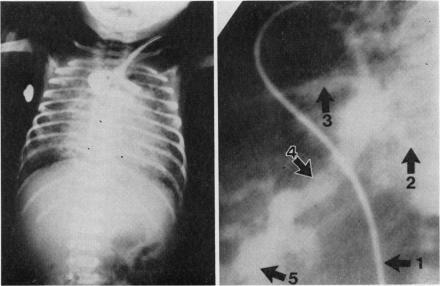

A boy aged 1 month presented with profuse rectal bleeding. Chest x-ray film showed pulmonary oedema and at cardiac catheterisation infradiaphragmatic total anomalous pulmonary venous drainage to a dilated portal venous system was found. Ulcerated oesophageal varices were identified at necropsy after unsuccessful cardiac surgery. The late and unique presentation of this case is emphasised.

一名1个月大的男婴出现大量直肠出血。胸部X线片显示肺水肿,心导管检查发现膈下完全性肺静脉异位引流至扩张的门静脉系统。心脏手术后未成功,尸检发现食管静脉曲张溃疡。强调了该病例的晚期和独特表现。